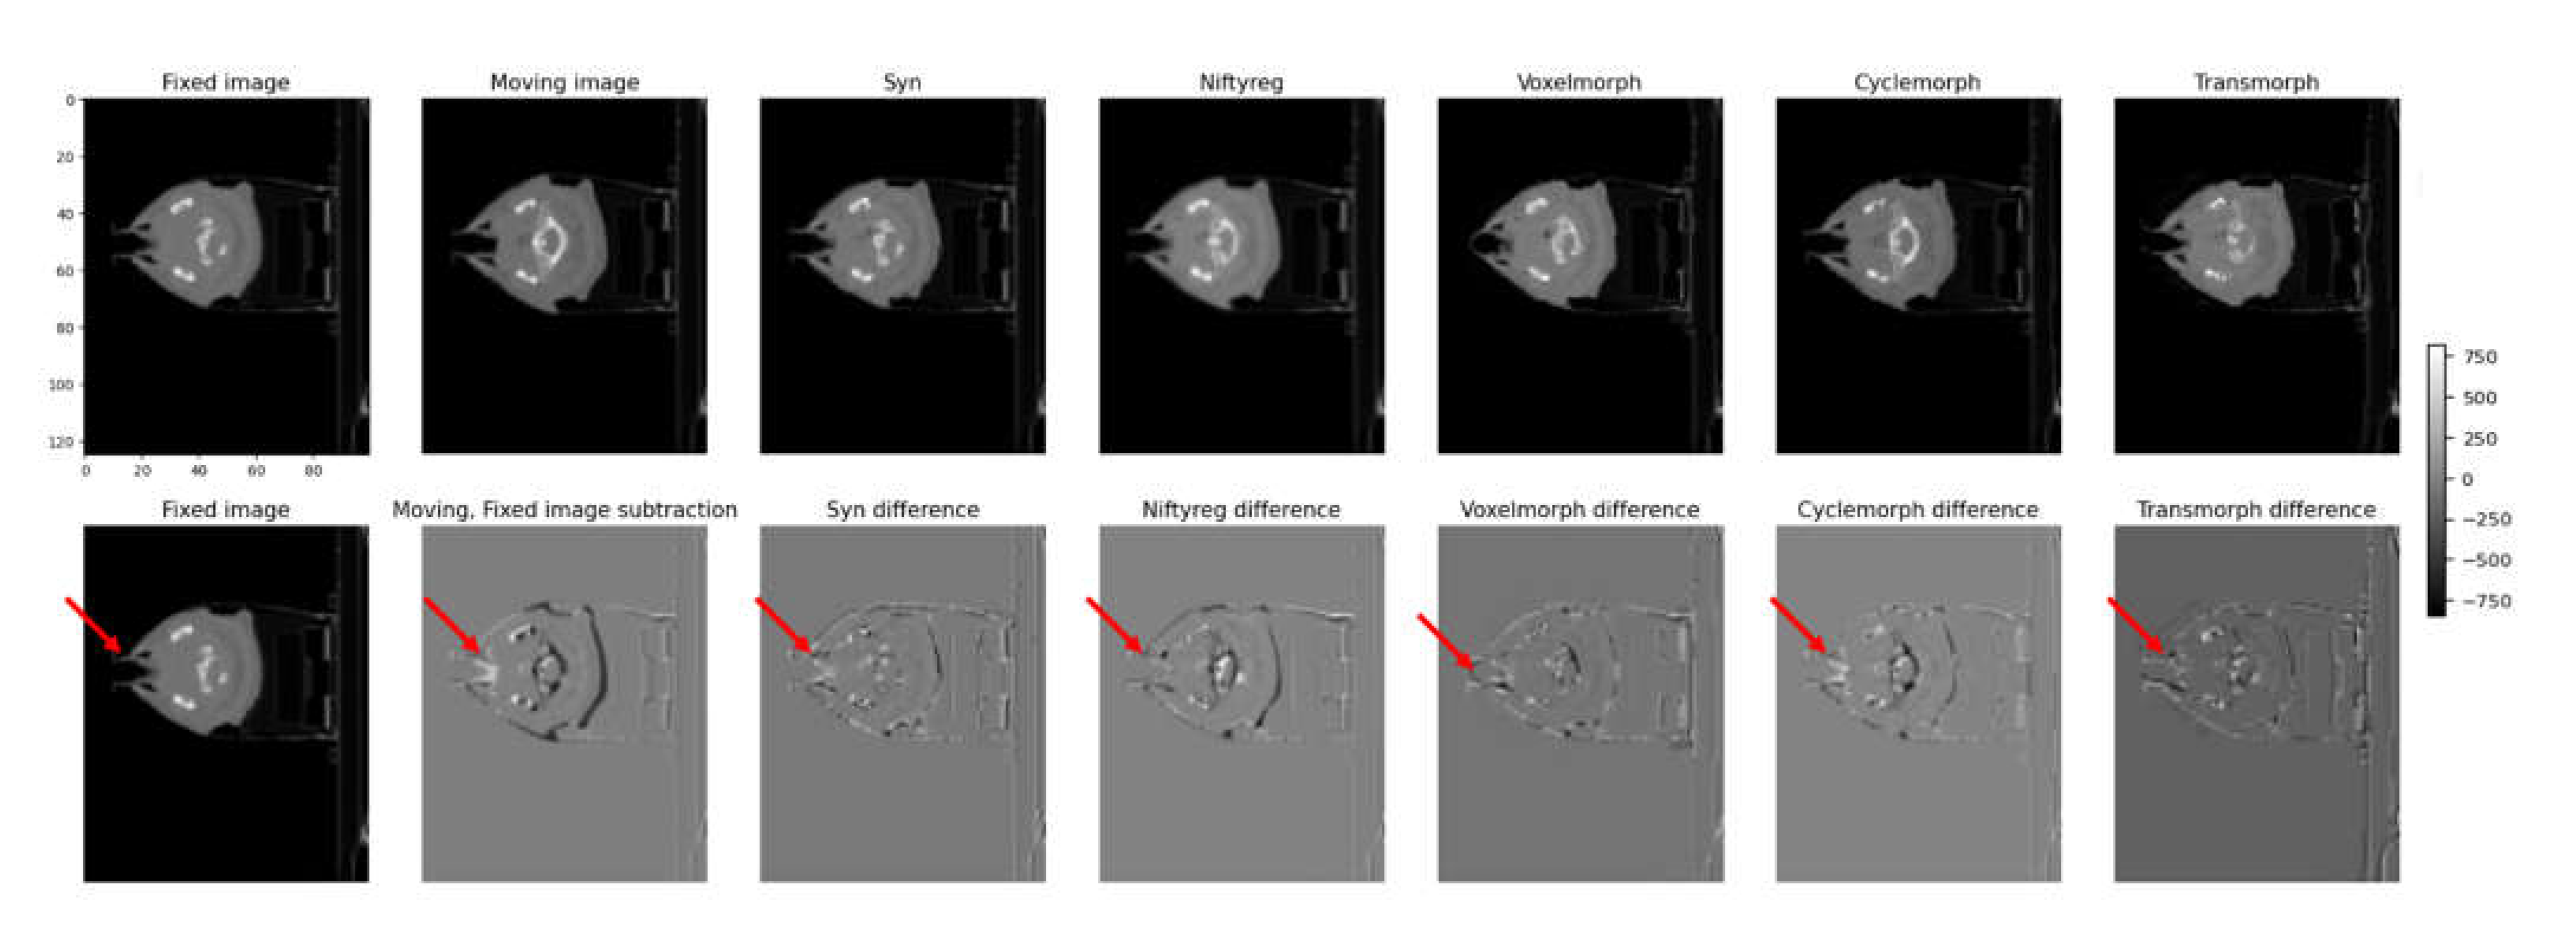

Figure 7 shows the fixed and moving image sequences of a patient wearing an assistive device due to lip surgery. The first row presents the transformed results for each model, while the second row shows the subtraction images between the transformed image and the fixed image. In the first row, each model's transformed results are displayed, indicating how well they align the moving image with the fixed image. The transformed images show the effects of the deformable image registration (DIR) algorithms on the patient's anatomy. The performance of each model can be assessed by comparing the alignment and accuracy of the transformed structures. In the second row, the subtraction images demonstrate the differences between the transformed image and the fixed image. These subtraction images allow for a visual comparison of the discrepancies and deviations between the transformed and fixed images, highlighting areas of misalignment or inaccurate deformation.

By examining both the transformed results and the subtraction images in Figure 6 it is possible to evaluate the effectiveness of each model in accurately aligning and deforming the moving image to match the fixed image in the context of a patient with an assistive device.

Figure 7. illustrates the fixed and moving image sequences of a patient wearing an assistive device due to lip surgery. The first row presents the transformed results for each model, while the second row shows the subtraction images between the transformed image and the fixed image.